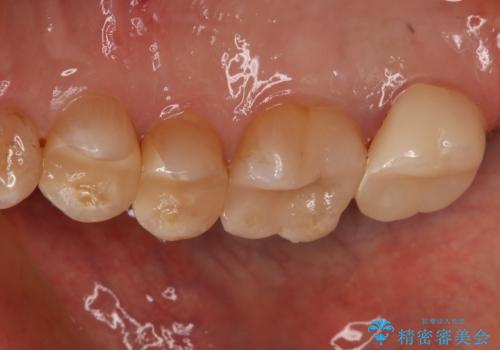

- かなり昔に入れた銀歯の部分のチェックをご希望でご来院されました。

上下ともに銀歯が多く入っており、その下に虫歯が疑われる状態でした。

詰め物の大きさや虫歯の状態から個々に材料と治療範囲を決定し治療に入りました。